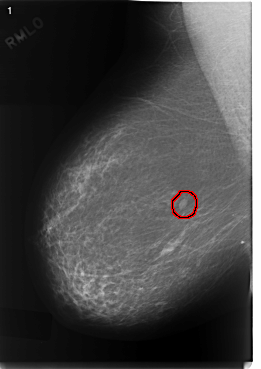

FILE: C_0331_1.RIGHT_MLO.OVERLAY

TOTAL_ABNORMALITIES 1

ABNORMALITY 1

LESION_TYPE MASS SHAPE OVAL MARGINS CIRCUMSCRIBED

ASSESSMENT 3

SUBTLETY 5

PATHOLOGY BENIGN

TOTAL_OUTLINES 1

BOUNDARY